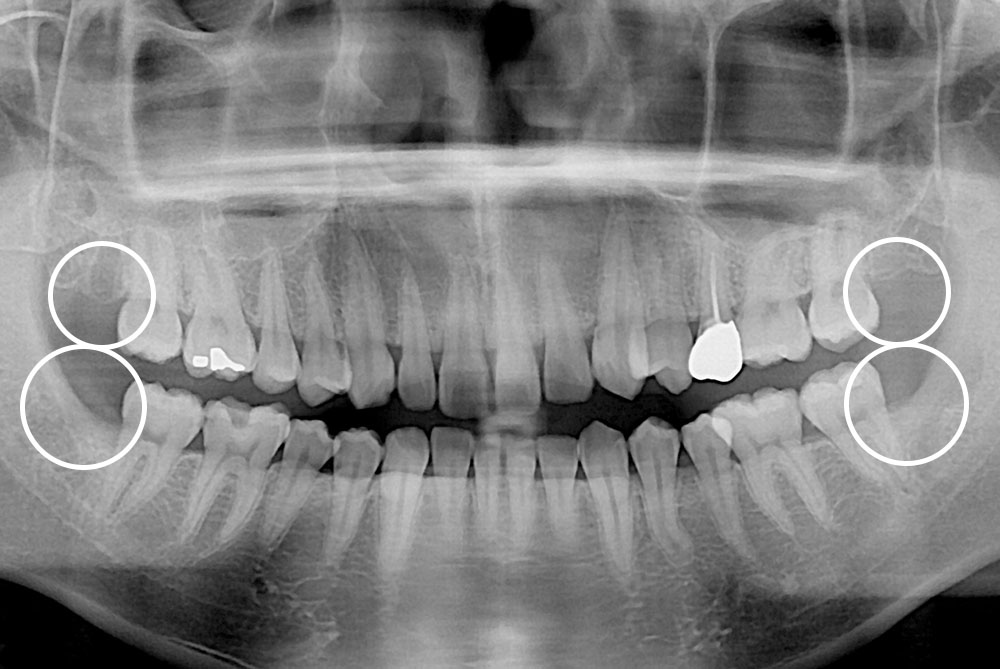

[사랑니] 매복 사랑니 발치

치료전 : 2019-10-09